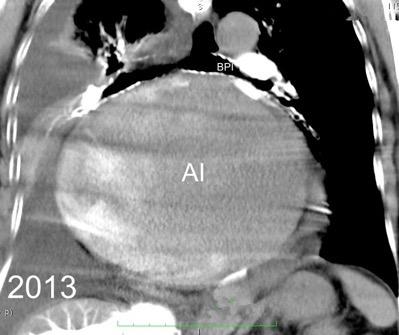

53. BPI .COMPRESIÓN Y DESPLAZAMIENTO HACIA ARRIBA DEL

55. BPI . COMPRESIÓN Y DESPLAZAMIENTO HACIA ABAJO DEL

La presencia de tumor o ganglios rodeando el BPI hace que este aparezca como mucho más nítido y definido.

Carcinoma microcítico..

Parálisis frénica. Atelectasia parcial de LSI.

Densidad baja uniforme del espacio. Pared interna de BPI-BI visible.

BPI sin alteraciones Ángulo carinal normal

Crecimiento AI

Ganglios Quiste broncogénico

Ganglios subcarinalesl Ángulo carinal normal